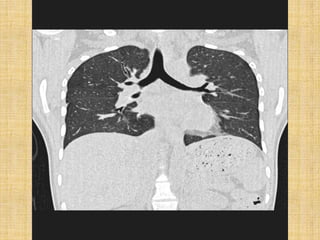

   Right lung is divided by major and minor fissure

into 3 lobes and 10 bronchopulmonary segments

   Left lung is divided by major fissure into 2 lobes

with a lingular lobe and 8 bronchopulmonary

segments

   The trachea (windpipe) divides into left and the

right mainstem bronchi, at the level of the sternal

angle (carina).

   The right main bronchus is wider, shorter, and more

vertical than the left main bronchus.

   The right main bronchus subdivides into three lobar

bronchi, while the left main bronchus divides into

two.

   The lobar bronchi divide into tertiary bronchi, also